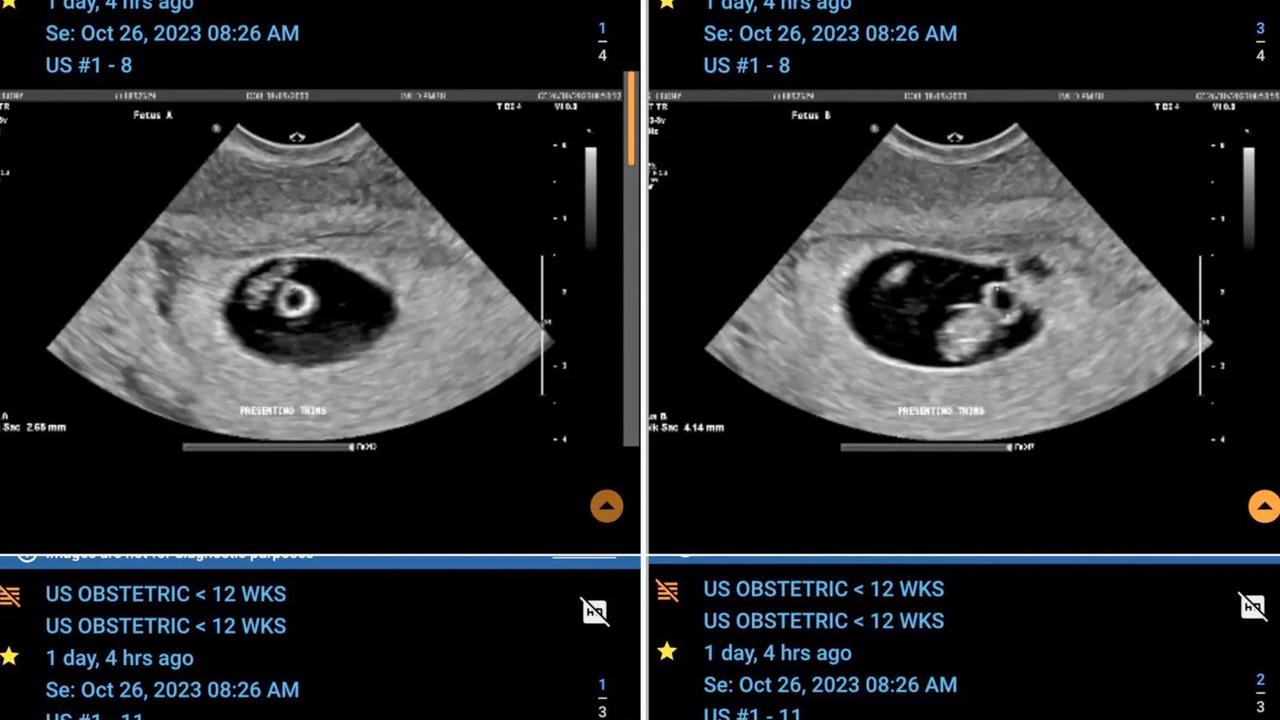

Seorang wanita Australia Ebony App merasa terkejut, setelah mengetahui bahwa dia sedang mengandung dua pasang anak kembar identik pada saat yang bersamaan. Ebony yang berusia 23 tahun dan pasangannya Jayden bersiap menyambut kedatangan empat bayi kembar identik pada bulan April mendatang.

"Dokter kami memberi tahu kami bahwa kehamilan kembar empat terjadi sekitar satu dari 700.000, dan kehamilan dua pasang kembar identik bahkan lebih jarang lagi," ungkap Ebony dalam wawancara dengan Caters News.

Perawat di rumah sakit bahkan mengatakan bahwa kehamilan seperti ini sangat langka, belum pernah ditemui dalam 30 tahun karirnya. Menurut AL.com, kemungkinan kehamilan dengan dua pasang anak kembar identik adalah sekitar 1 dari 70 juta.

Pasangan ini awalnya diberitahu, bahwa mereka mengandung anak kembar pada pemindaian pertama di bulan September. Namun, sebulan kemudian dokter menemukan ada dua bayi di setiap kantung, mengindikasikan bahwa Ebony mengandung dua pasang anak kembar identik.